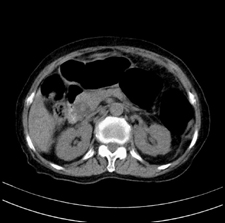

患者,女,75岁。腹痛,体黄5日,膝胸位时腹痛缓解。肝功能明日出来。彩超提示胆总管占位,未见血流信号。心电图提示s-t段改变。患者体质较弱,未能增强。

胆总管上段,腔内有软组织密度影 ,ct值36-44hu。大家看有没有胆管癌的可能。

典型胆总管多发结石;增强扫描前后ct值是否发生改变是鉴别结石与占位的依据。